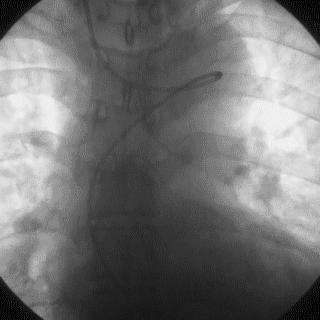

➢ CASE 1

➢ CASE 2

右冠起源异常,开口于左冠窦

➢ CASE 3

AL1.0

➢ CASE 4

➢ CASE 5

升主动脉造影未见桥血管显影,原位血管造影也没发现竞争血流迹象,可以确定桥血管已闭塞,必要时可以借助冠脉CTA辅助诊断